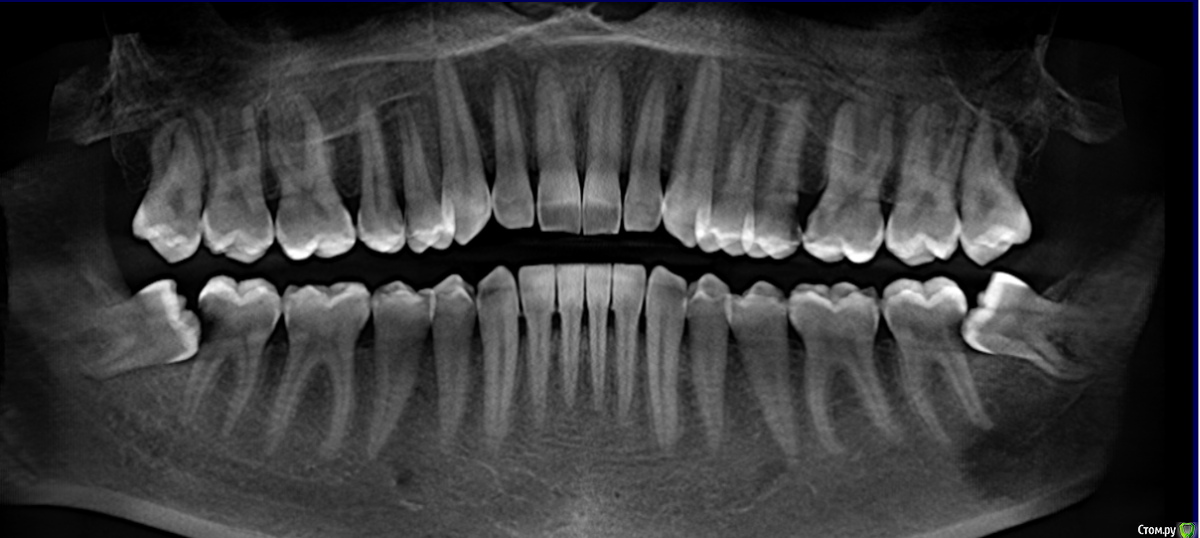

tarian1 Опубликовано 26 июня, 2019 Поделиться Опубликовано 26 июня, 2019 Врач по снимку сказал, что пульпит в 5 зубах, и надо удалять нервы + ставить коронки. Верно ли мне сказали диагноз?,Зубы не болят, чувствительноcть на перепады температуры, боль быстро проходит. Болел только один, собственно из-за чего пошел к врачу. спасибо. Ссылка на комментарий

red_butler Опубликовано 27 июня, 2019 Поделиться Опубликовано 27 июня, 2019 Верно ли мне сказали диагноз?, только по одному снимку, к тому же панорамной реконструкции из Кт, диагнозы не поставитьЧто я вижу1. необходима профессиональная гигиена2. лечение 1.5 2.5 2.6 3.7 и 4.73. удаление 3.8 и 4.8 1 Ссылка на комментарий

AndyAndy Опубликовано 28 июня, 2019 Поделиться Опубликовано 28 июня, 2019 Насчёт депульпирования вам сказали все правильно, судя по снимкам. Насчёт коронок будет понятней после препарирования кариозных полостей и оценки объёма оставшихся твёрдых тканей зубов 1 Ссылка на комментарий

St. Опубликовано 30 июня, 2019 Поделиться Опубликовано 30 июня, 2019 Зубы не болят, чувствительноcть на перепады температуры, боль быстро проходит. Это хорошо. Тем не менее не оттягивайте визит на лечение, разрушения обьемные и зубы могут заболеть в любое время 1 Ссылка на комментарий